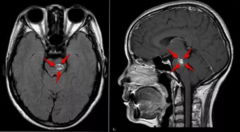

脑干海绵状血管瘤(CMs)是大脑较关键区域之一的一种病变,对于神经外科医生和患者来说都是一个挑战。这一亚组约占全部脑海绵状血管瘤(CCMs)的15%,手术切除、放射治疗或保守治疗...

脑干海绵状血管瘤较多见于脑桥,其次为中脑、中脑桥、延髓。在脑干内生型病变中,海绵状血管瘤是适合手木切除的病变。它们在组织学上属良性,不含神经组织。如能全切除,则为...

脑海绵状血管瘤 是指长在脑内的血管畸形,其中脑干部位的海绵状血管瘤是位置较深、手术难度较大的 颅内海绵状血管瘤 ,年出血率为4.6%,再出血间隔为3天-151个月。脑干海绵状血管...

脑海绵状血管瘤(CH)报道发现于中枢神经系统的任何部位。由于计算机断层扫描和磁共振成像的使用越来越多,近年来诊断出了更多的先天性心脏病。然而,脑室内CHs的位置并不常见...